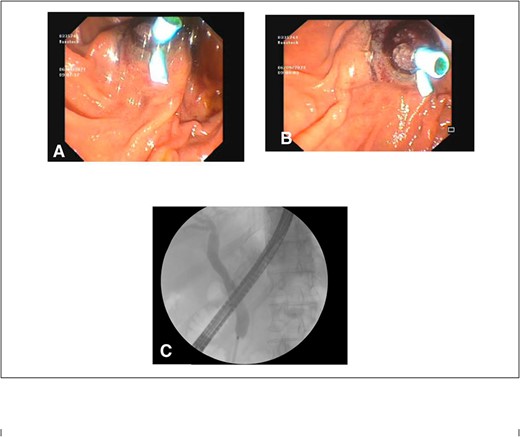

After consultation with our Hepatobiliary service, the consensus was for the patient to undergo an urgent ERCP. Intraoperatively, a duodenoscope was introduced through the mouth and was advanced to the duodenum at the ampulla of Vater. The major papillae were bulging and a malignant appearing infiltrative mass was visualized. A tapered tip cannula was inserted through the ampulla and contrast was injected, revealing a patent PD and a single 18-mm long stenosis of the distal third of the CBD with significant dilatation of the proximal CBD and intrahepatic ducts (Fig. 2). A 10Fr 7-cm transpapillary plastic stent was inserted with a single internal flap, 5.5 cm, into the CBD. The biliary pancreatic junction was biopsied with cold forceps for histology. Cholangiopancreatography revealed the stent was in good position with good flow of contrast into the duodenum beyond the filling defect (Fig. 3).

(A) and (B) malignant appearing soft tissue infiltrative mass within the ampulla of Vater seen on ERCP; (C) cholangiopancreatography showing stenosed distal third of the common bile duct along with a patent pancreatic duct.